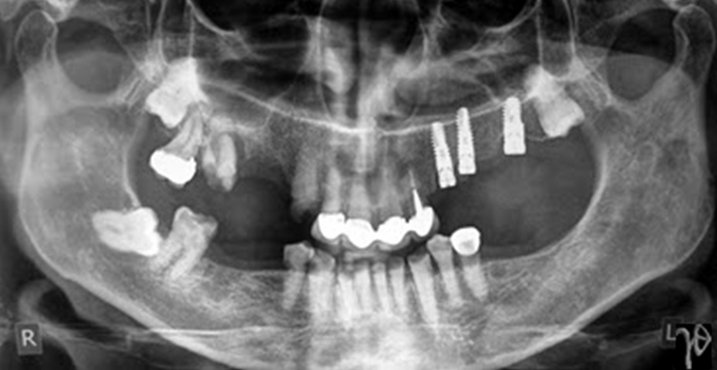

Εικόνα: Σε περίπτωση ακτινοθεραπείας τα εμφυτεύματα μπορούν να τοποθετηθούν πριν την έναρξη της, όπως εδώ, όπου τα εμφυτεύματα είχαν τοποθετηθεί δύο μήνες ενωρίτερα. Ένα χρόνο μετά την ολοκλήρωση της ακτινοθεραπείας (θεραπευτική δόση), για κακοήθη νεοπλασία της μαλακής υπερώας, η οστεοενσωμάτωση παραμένει χωρίς επιπλοκές σε αντίθεση με τις εμφανείς μετακτινικές οδοντικές καταστροφές.